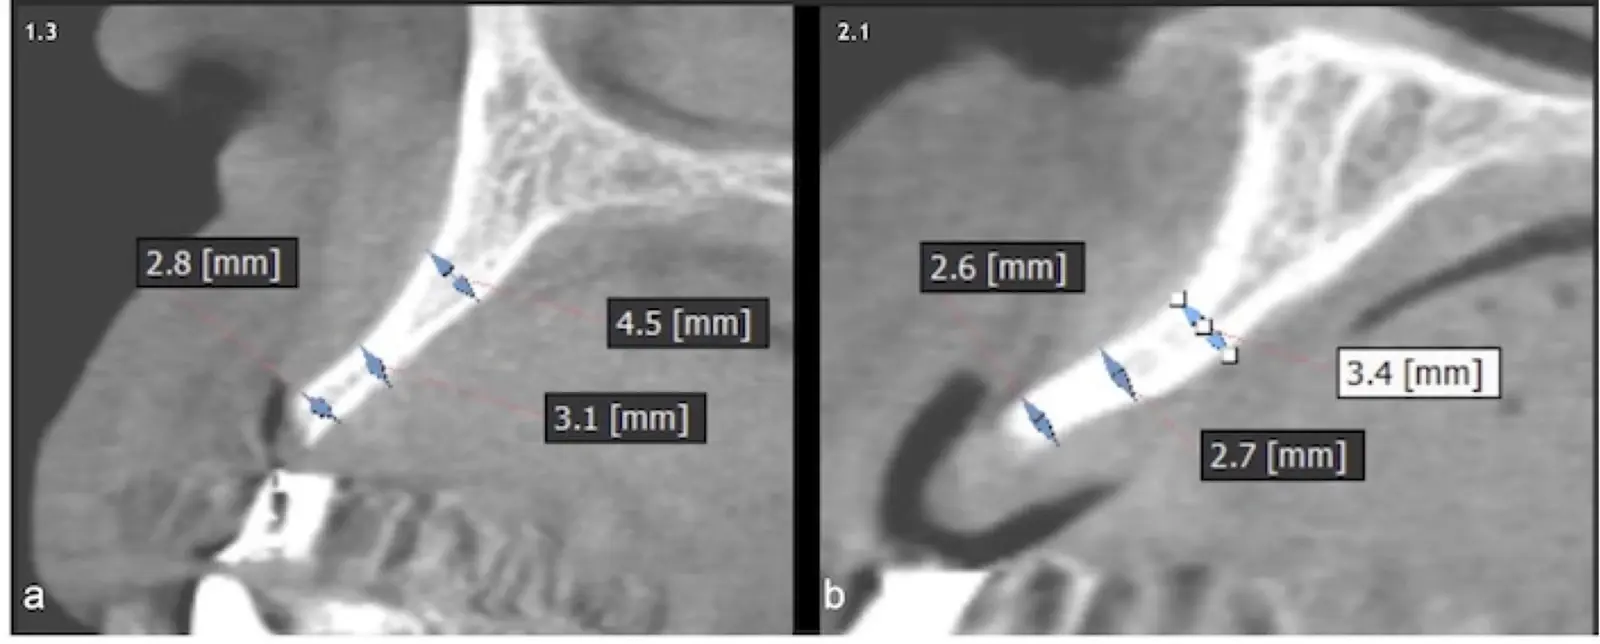

Figura 19. Tomografía computarizada de la zona receptora. Pieza 1.3 (a). Pieza 2.1 (b).